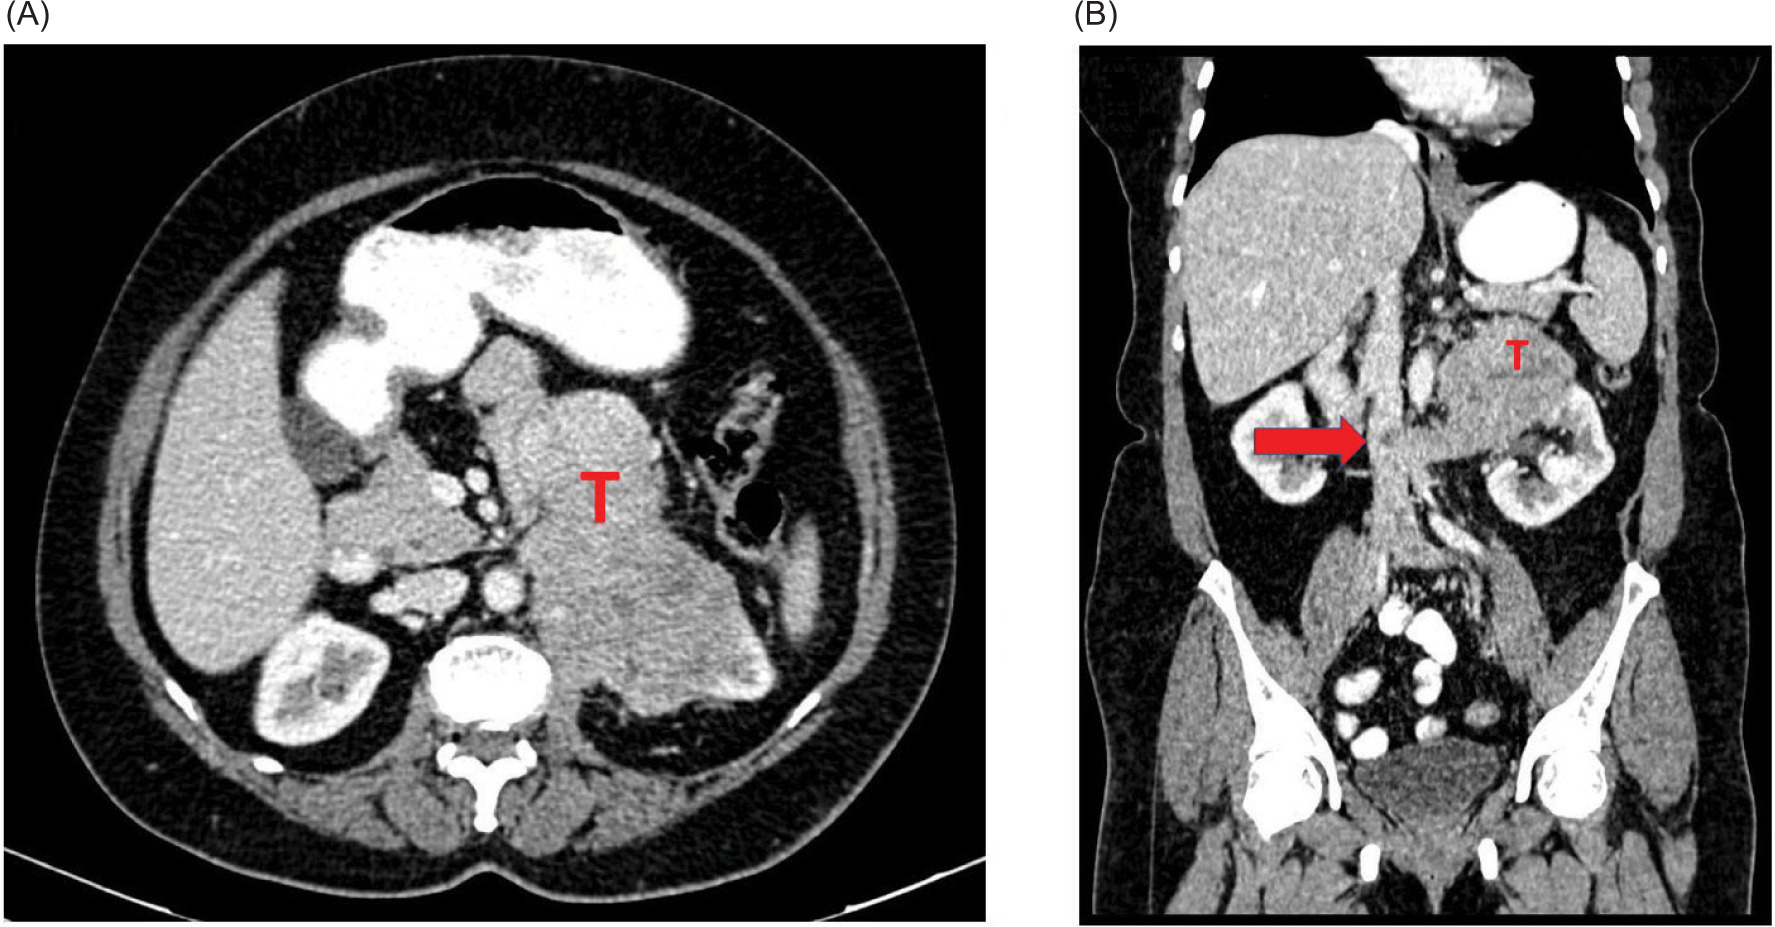

A 60-year-old post-menopausal female presented with recent onset left flank pain. Contrast enhanced computed tomography (CECT) abdomen revealed a 11-cm partly cystic, heterogeneously enhancing left renal mass abutting the aorta with a thrombus in the left renal vein extending to the inferior vena cava (IVC) (Figure 1A,B). As the mass did not conform to the appearance of a conventional renal tumor on imaging, Image-guided percutaneous biopsy was performed. This showed fibroconnective tissue infiltrated by sheets of atypical cells showing moderate cytoplasm, hyperchromatic pleomorphic nuclei with inconspicuous nucleoli, suggesting a poorly differentiated malignant tumor (Figure 2A,C). Immunohistochemistry was positive for vimentin, smooth muscle actin (SMA), keratin, caldesmon and weakly positive for calponin, with 40% Ki 67 positivity, suggesting a diagnosis of malignant glomus tumor (Figure 2D,F). After informed decision, the patient and family elected to proceed with surgery. However, intraoperatively, the left renal mass was found to infiltrate the pancreas, duodenum, aorta, and root of the colonic mesentery due to which surgery was aborted. Biopsy obtained intraoperatively again confirmed diagnosis of left renal malignant glomus tumor. She had an uneventful post-operative recovery. Options of treatment were reviewed by the multidisciplinary board. In light of no proven benefit for systemic therapy, she was referred for supportive care. She was under follow-up and she expired after 7 months due to progressive disease.

Figure 1: Computed tomography images showing the heterogeneously enhancing left renal mass involving the left renal vein and IVC and abutting the aorta. (A) Cross-sectional image and (B) Sagittal image. (T – Tumor), arrow pointing to the inferior vena cava (IVC) thrombus.